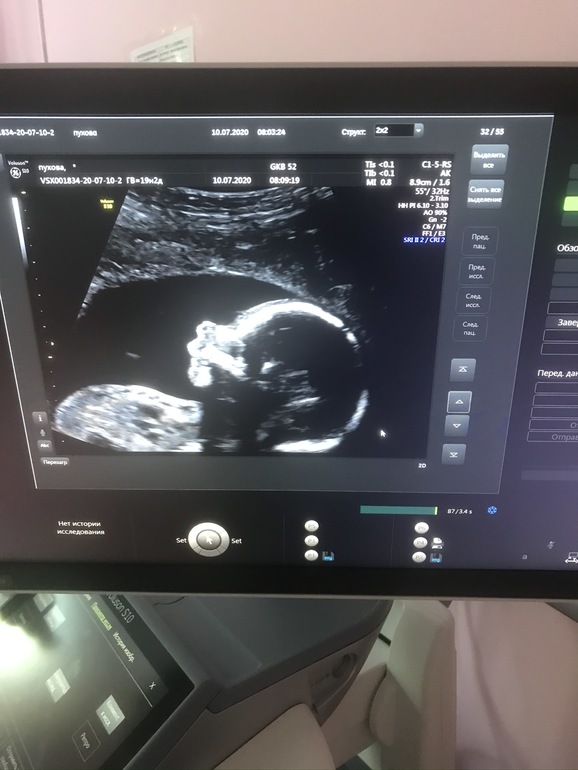

Вот она наша крошка 💓

Сегодня 19 и2 дн - вес малышки 260 гр

Малышка лежит головой вниз. Шейка закрыта, длина 37 мм. Кровотоки в норме. Все остальные показатели в норме.